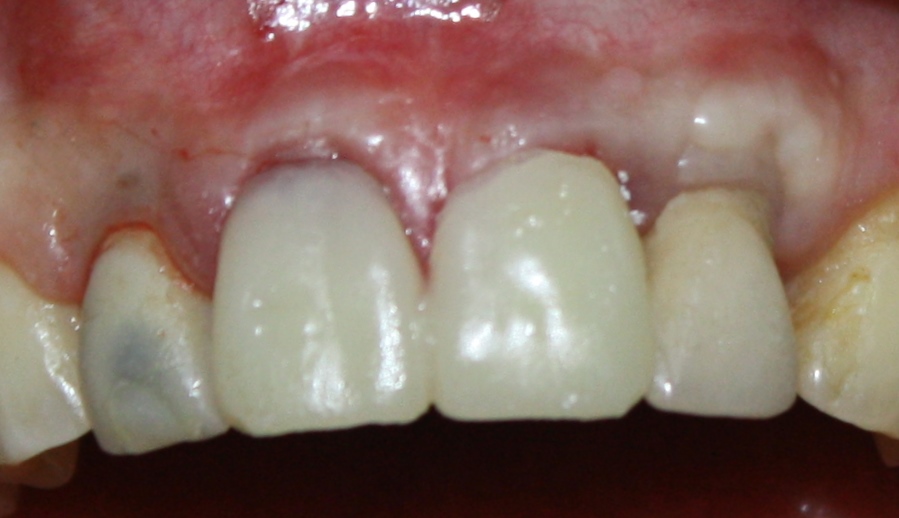

И вот, в жизни Марии наступил долгожданный день — окончательная фиксация керамических коронок на установленные имплантаты:

При этом, она ни дня не оставалась без зубов, была полностью социализирована и жила обычной жизнью. Спустя 5 месяцев после удаления, поставленную Марией клиническую задачу можно считать решёной. Но это с её точки зрения. С нашей же, всё самое интересное только начинается.

Вот клиническая картина и рентгенологический контроль через 2,5 года после имплантации и протезирования:

С точки зрения функционала, Мария не чувствует принципиальной разницы между естественными здоровыми зубами и коронками на имплантатах (последние она находит «более симпатичными») По её словам, она и думать забыла об имплантатах, а прошлые мучения с зубами кажутся ей «ночным кошмаром».